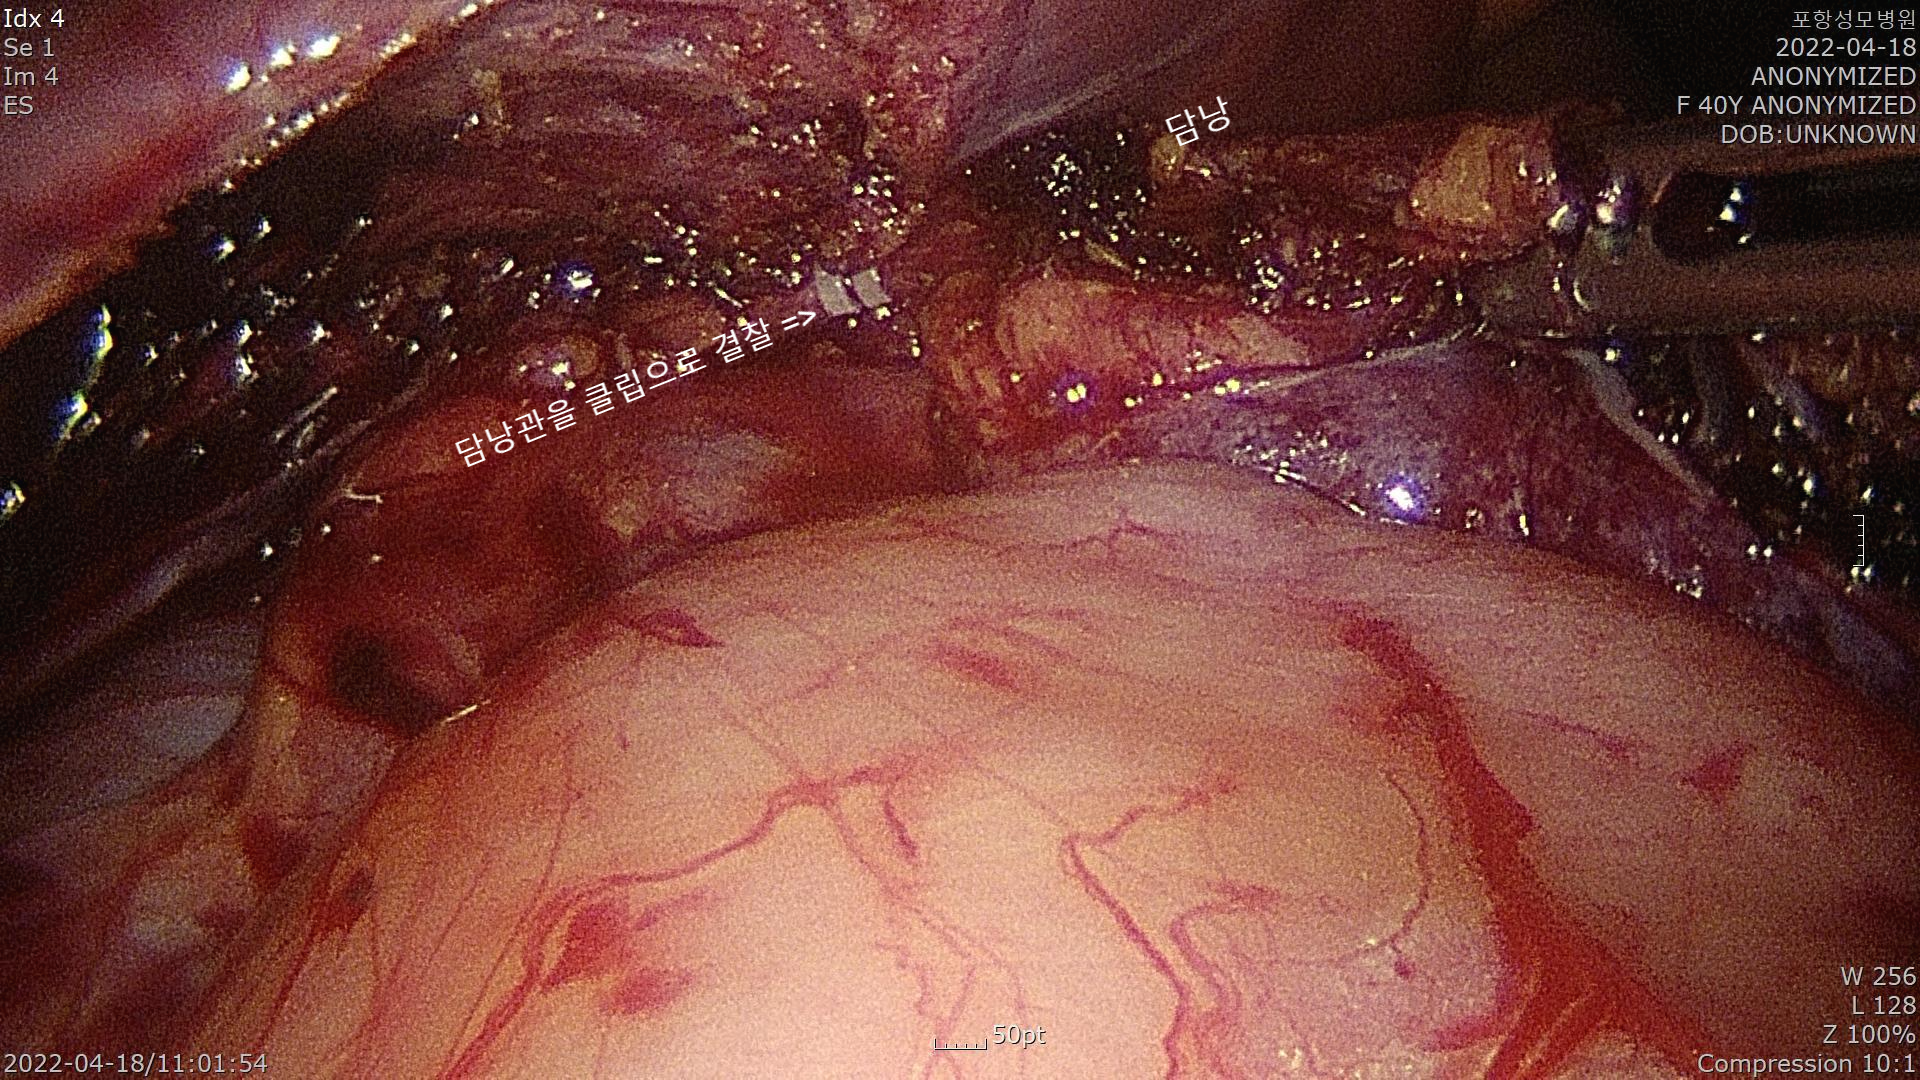

담낭관을 클립으로 결찰한 모습입니다.